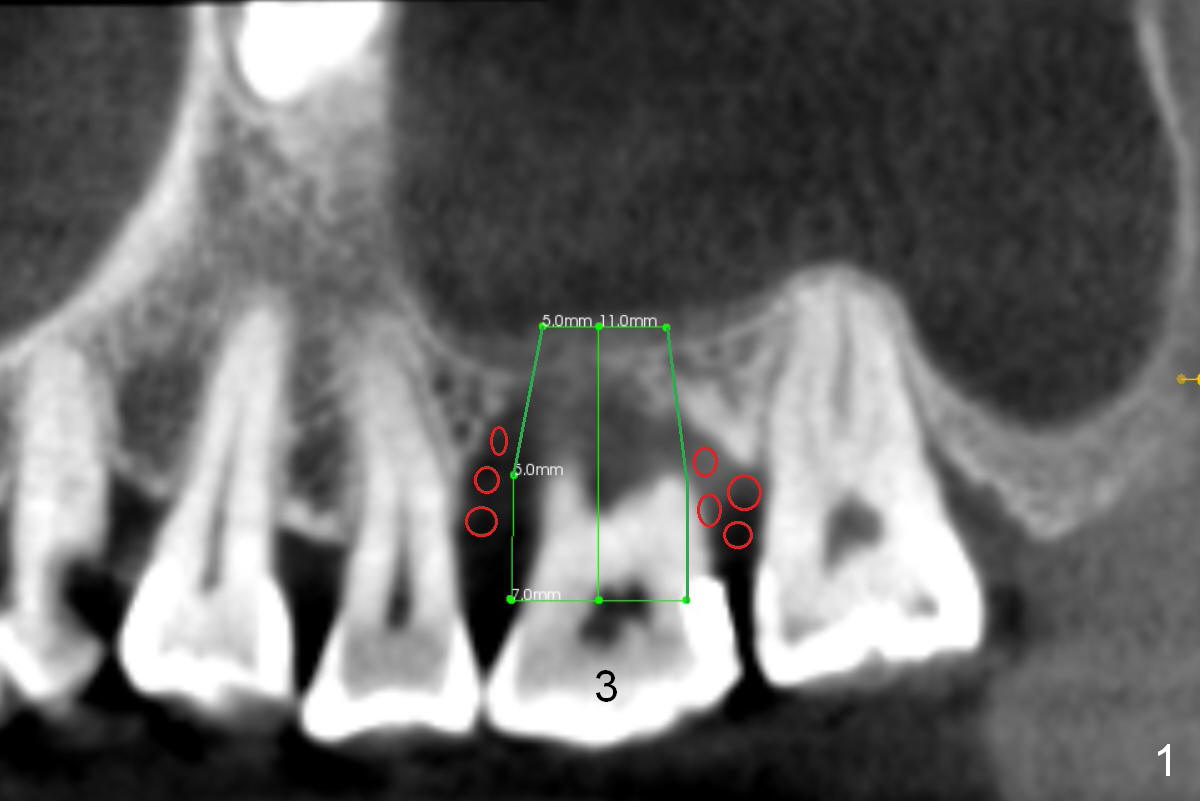

A 52-year-old lady (ZJ) has severe bone loss at #3 (Fig.1 (CT sagittal section)). After extraction, the socket will be treated with Metronidazole. A small amount of apical bone is available for primary stability; the bone density is also low (300-500 Hounsfield Units, Fig.3 (axial section)). Use RT2,3 for creating osteotomy and bone condensation, followed by 4.5-7x14 mm taps (11 mm deep; gingival margin). Prior to bone grafting (Fig.1,2 (coronal section) red circles), apply Endogain against the root surface of the neighboring teeth.